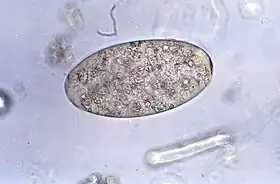

![]() Ovo do parasita F. buski | |||||||||||||||